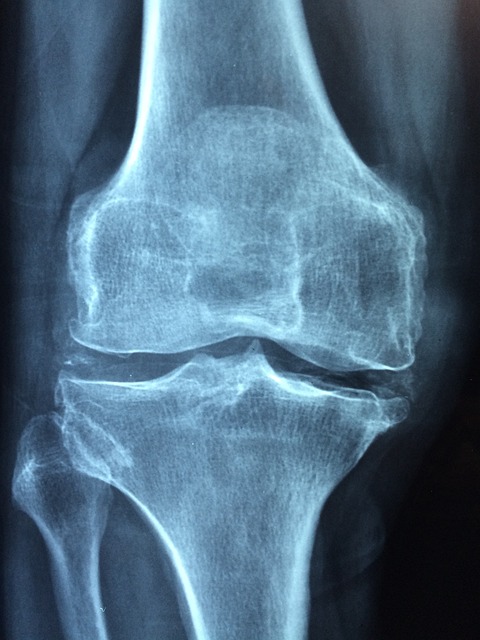

SBS 좋은아침 똑똑똑! 고민상담소 2024년 6월 6일: 산고와 맞먹는 통증! 퇴행성 관절염

SBS 좋은아침 똑똑똑! 고민상담소 2024년 6월 6일: 산고와 맞먹는 통증! 퇴행성 관절염으로 방송되었는데요! 퇴행성 관절염은 많은 사람들에게 심한 통증을 유발하는 만성 질환이에요. 특히 국내 45세 이상 인구에게 흔한 병이죠. 이 글에서는 퇴행성 관절염의 원인과 관리 방법에 대해 알아보겠습니다.

국내 45세 이상 만성 질환 1위 관절염

관절염은 45세 이상의 많은 사람들에게 영향을 미치는 만성 질환이에요. 특히 나이가 들수록 관절의 퇴행이 빨라져 더 많은 사람들이 이 질환으로 고통받고 있어요.

퇴행성 관절염은 어떤 증상이 있나요?

퇴행성 관절염의 주요 증상은 관절 통증, 부종, 강직함 등이 있어요. 특히 아침에 일어났을 때 관절이 뻣뻣한 느낌이 들 수 있어요.